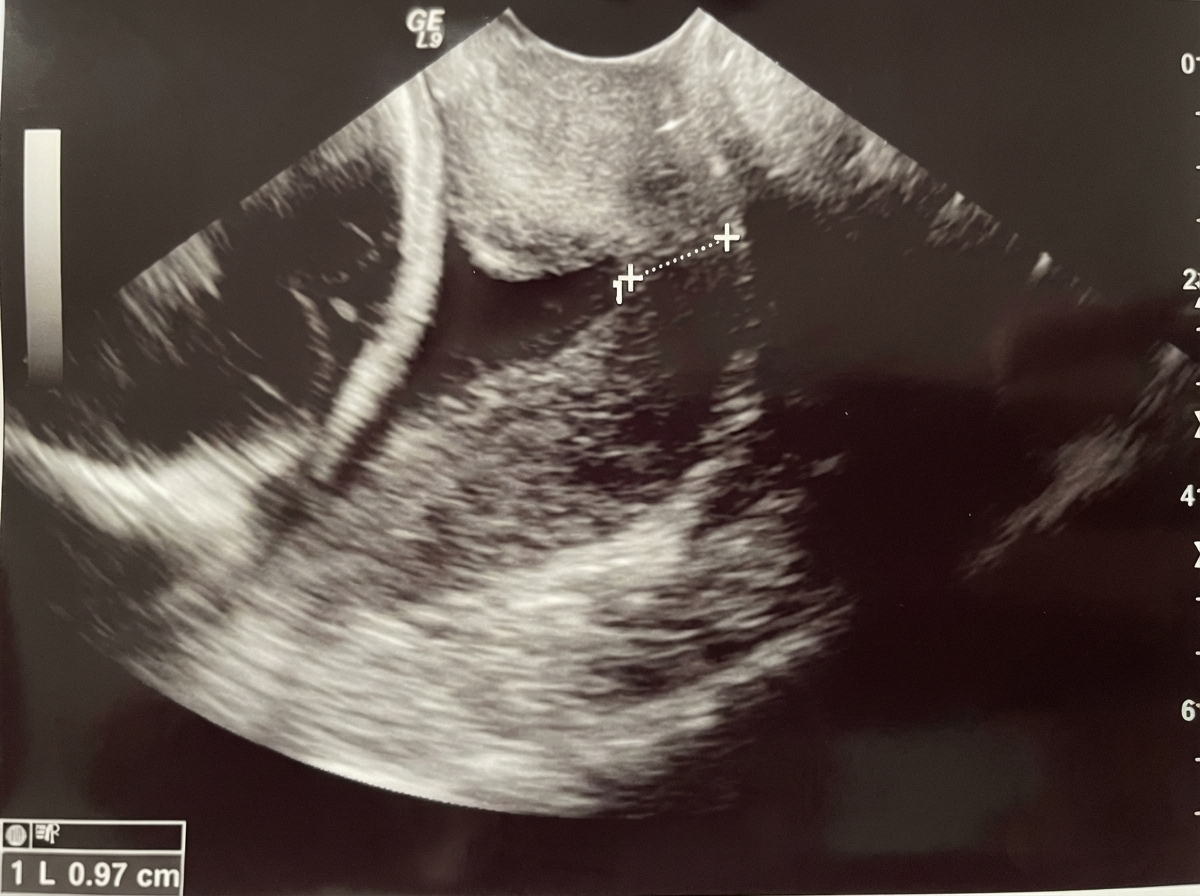

A gravida 3 female with a history of two prior second-trimester abortions associated with painless cervical dilatation presents with Level II ultrasound findings. What is the most appropriate management?

Explanation: ***Apply McDonald suture*** - History of two prior **second-trimester abortions** with **painless cervical dilatation** indicates **cervical incompetence**, requiring **cervical cerclage**. - **McDonald cerclage** is the standard procedure for cervical incompetence, using a **purse-string suture** around the cervix to provide mechanical support. *Administer progesterone* - **Progesterone** is used as adjunctive therapy for **short cervix** but is not the definitive treatment for **cervical incompetence**. - It may help maintain pregnancy but cannot provide the **mechanical support** needed to prevent cervical dilatation. *Apply Fothergill suture* - **Fothergill suture** refers to the **Manchester operation** for **uterovaginal prolapse**, not cervical incompetence. - This procedure involves **amputation of the cervix** and **cardinal ligament shortening**, which is inappropriate for pregnancy management. *Wait and watch* - **Expectant management** is inappropriate given the clear history of **recurrent second-trimester losses** due to cervical incompetence. - **Level II ultrasound** likely shows **cervical funneling** or **short cervix**, indicating active cervical changes requiring immediate intervention.